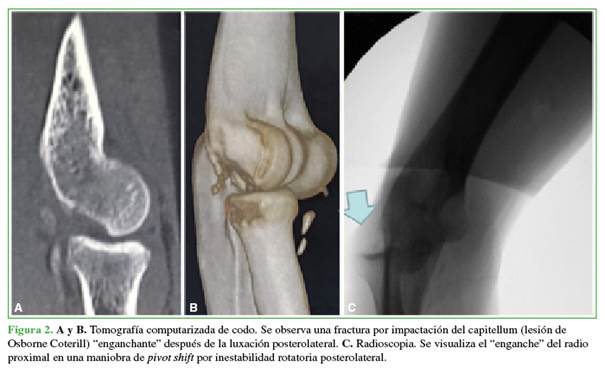

Es preciso sospechar una inestabilidad rotatoria posterolateral crónica descrita en 1991, por O’Driscoll, para poder diagnosticarla y planificar su tratamiento. En estos casos, se impone una reconstrucción ligamentaria.24 En ciertas ocasiones, según el tiempo de evolución y la cantidad de episodios de luxación, se acompaña de una fractura por impactación del capitellum descrita por Osborne y Coterill, en 1966. No siempre es necesario tratar este defecto óseo con un injerto asociado a la reconstrucción, aunque esto provoque un enganche del radio al luxarse (Figura 2).25